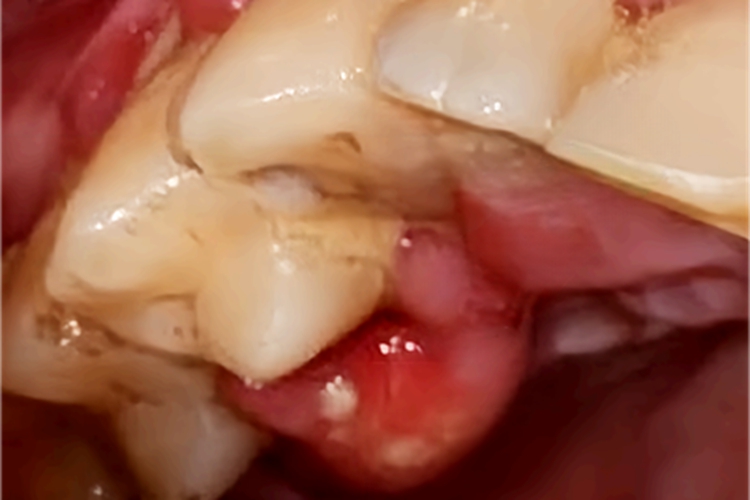

急性牙周脓肿的皮损可以表现为脓包样,呈椭圆形或半球状,明显突起于周围黏膜,大小不等,扪诊可有波动感,挤压有脓液流出,伴有疼痛或异物感。

急性牙周脓肿主要是牙周炎发展到晚期导致深牙周袋,袋内出现化脓性炎症,脓液不能及时排出,从而形成袋壁软组织内的脓肿。诱发因素包括机体抵抗力下降、严重的全身疾病、洁治或刮治时动作粗暴等。